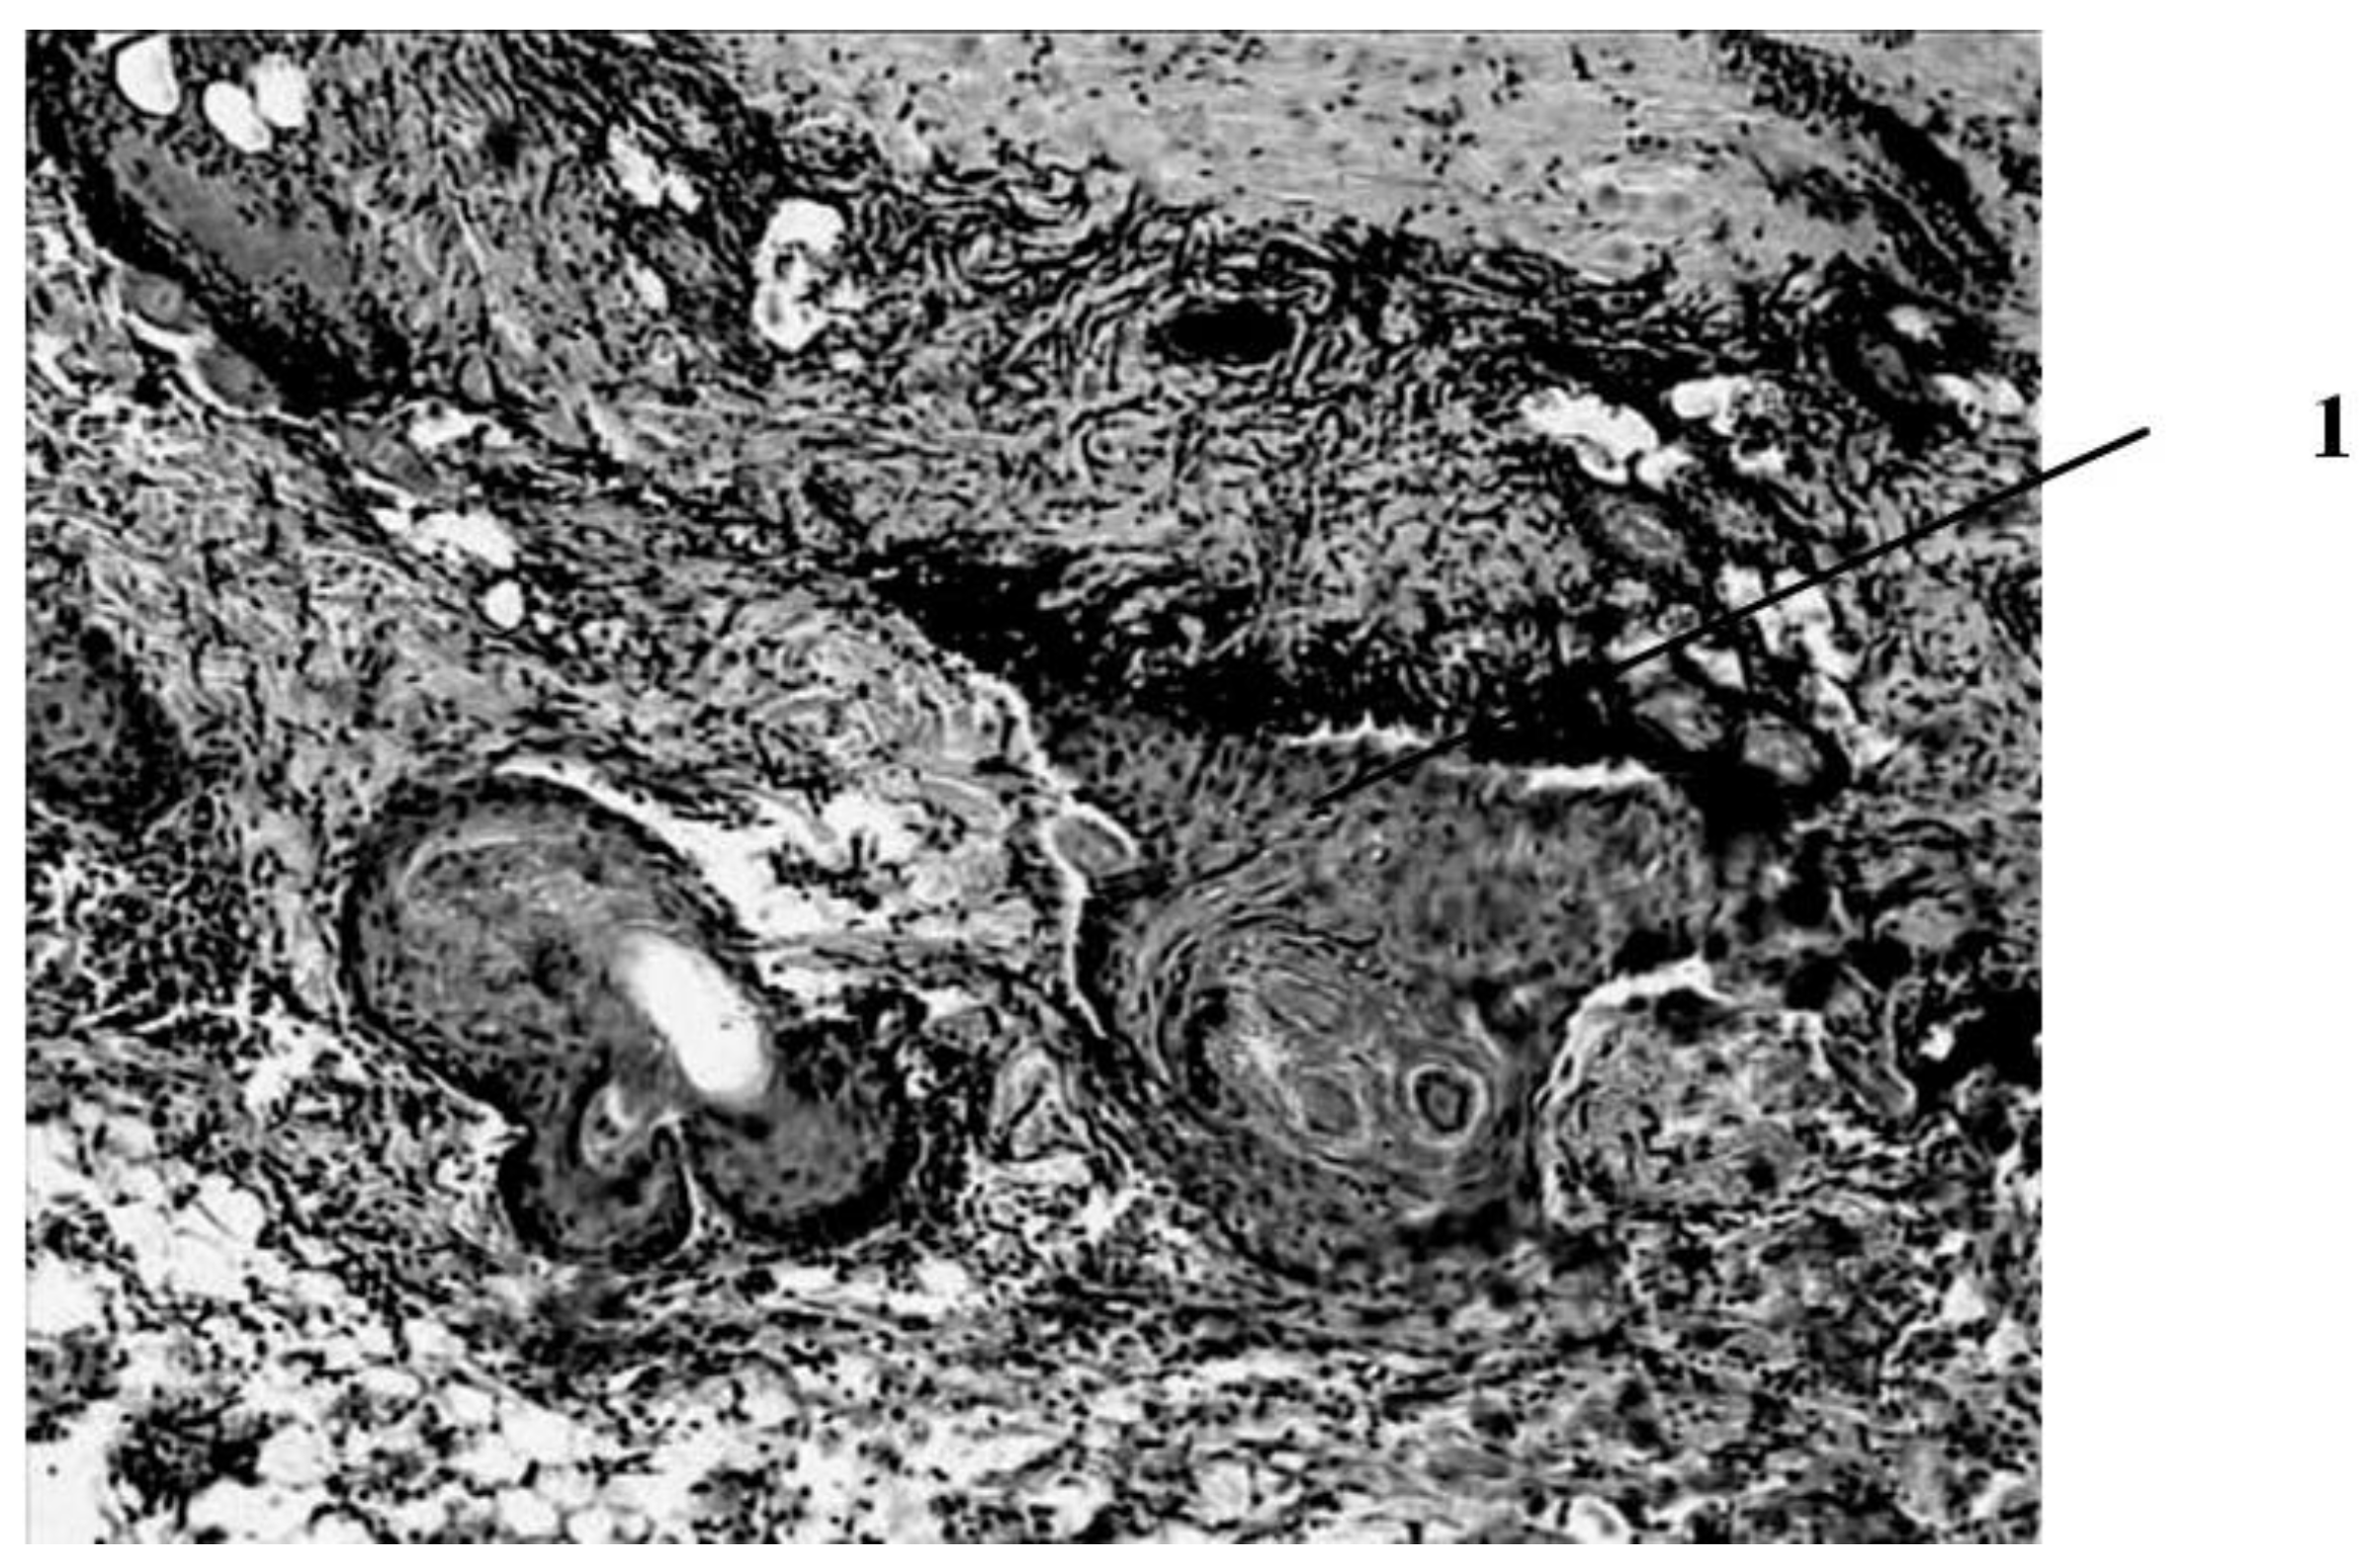

According to the results of histological examination, it was found that the first day after the injury, the histological picture in the edges of wounds in animals of all three groups had no differences (Figure 1). In all preparations, there is a lesion of the epidermis (necrosis and necrobiosis), dermis (papillary and mesh layers), manifested by the loss of the usual fibrous structure of the connective tissue of the dermis and transformation collagen fibers into a solid homogeneous mass, as well as edema and hemorrhages in loose connective tissue and adipose tissue located above the layer of the skin’s own muscle.

The blood vessels passing through here are often also necrotic, containing red blood clots. The muscle fibers of the skin’s own muscles are in a state of dystrophy: swollen, often vacuolated. There are no cores in individual fibers. In the loose connective tissue located under the muscle layer, there is fullness, puffiness, as well as an increased number of cells, among which leukocytes and macrophages predominate.

Figure 1. Histological picture of the wound on the first day after the burn (typical picture for rats of all groups). Deep burn with necrosis of the epidermis, papillary and mesh layers of the dermis, as well as necrobiosis of the muscle fibers of the skin’s own muscle. Stained with hematoxylin and eosin. magn. ×50.